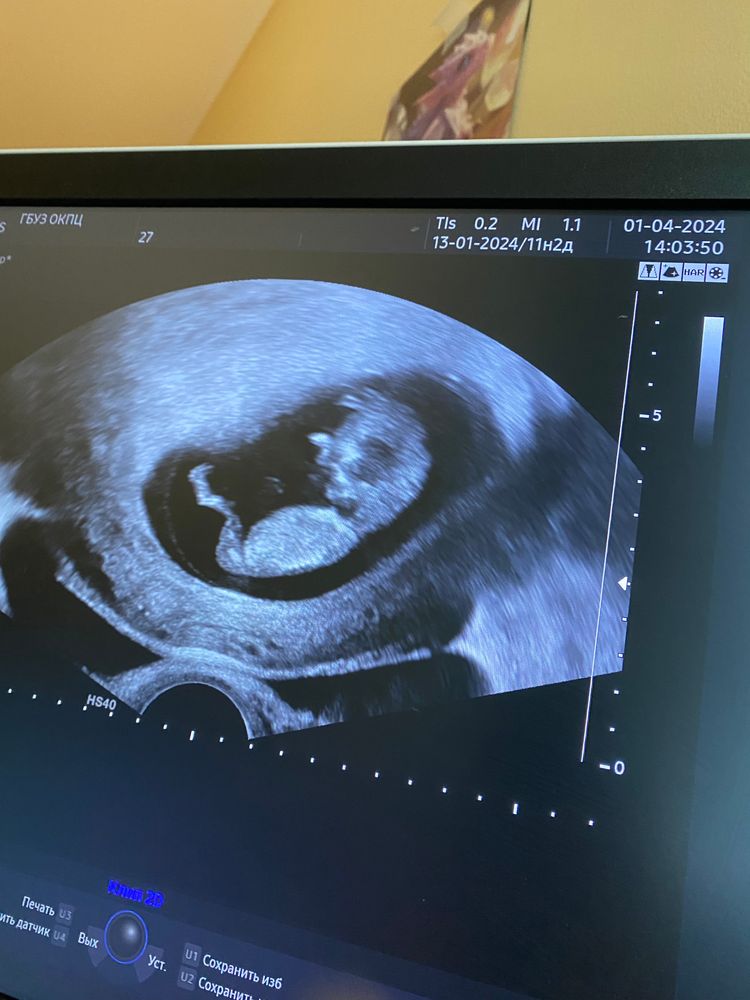

Кто в домике живет?🥰

УЗИ, КТГ, доплерДевочки! У меня двенадцатая неделя беременности. Нахожусь в стационаре, были коричневые выделения, положили на сохранение.

Скорее всего выделения были со второго рога ( матка двурогая).

Вчера сделали УЗИ, погадаем кто в домике живет? Малышок или малышка?

Тут не вижу полового бугорка, поэтому только можно пальцем в небо тыкнуть.)

Сложно понять, но если то, что я вижу это половой бугорок, то у вас мальчик)))👦